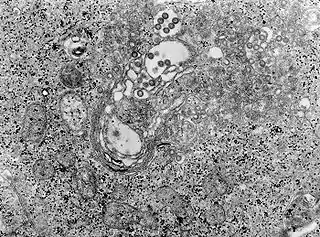

Los viriones son esféricos, sin envoltura, con diámetros de 90-100 nm y no contienen proteínas de matriz.